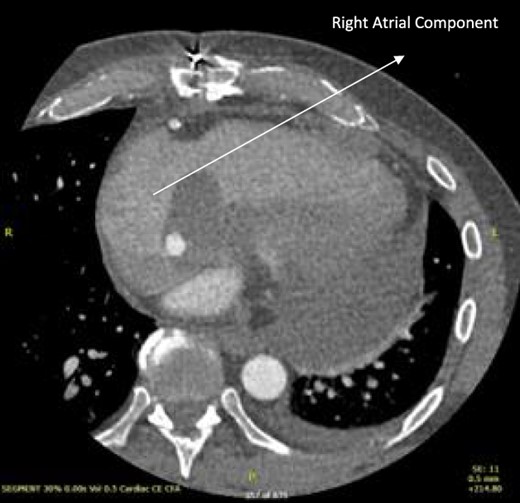

A 52-year-old gentleman was admitted to a district general hospital for shortness of breath causing type 1 respiratory failure with oxygen saturations of <90% despite high flow oxygen. His past medical history was unremarkable, and he was usually fit and well. A CT Pulmonary Angiogram (CTPA) was undertaken, which showed a heterogeneous oval-shaped lesion measuring 15 × 9 × 14 cm3 between the heart and the diaphragm, with a median attenuation of 35 HU and no enhancement during the arterial phase. Further solid lesions of 14 mm in the right lower lobe and 5 mm in the right upper lobe raised the suspicion of a primary cardiac sarcoma with pulmonary metastasis. This is shown in Fig. 1. Subsequent urgent CT staging (Fig. 2) was undertaken, which confirmed an indeterminate space occupying the inferior pericardial space, right atrial (RA) filling defect and anterior nodular pericardial thickening. No intra-abdominal or bone lesions were identified. An echocardiogram also confirmed these finding with the addition of no flow through the tricuspid valve (TV), as shown in Fig. 3.

CTPA showing oval-shaped heterogenous lesion as well as RA filling defect.

CT thorax-abdomen pelvis, depicting the RA filling defect as well as pericardial bulk.